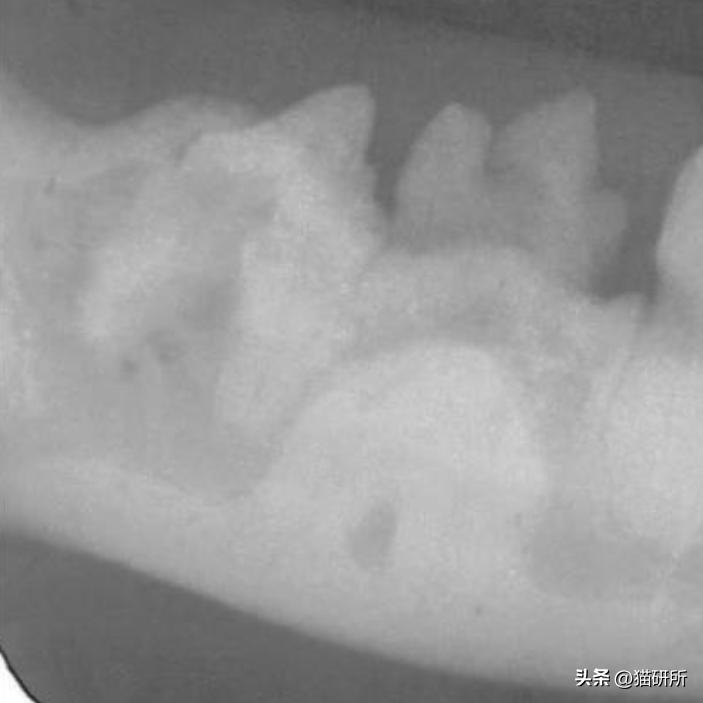

· 首先,猫咪会在换牙期过后,仍没有换牙或长出双排牙齿;

· 随后,因为牙齿太多太拥挤,可能出现咬合不齐、牙釉质损伤、牙龈炎、牙周炎,甚至牙髓炎的问题;

牙龈炎和下颌肿胀的PADS患猫

图自:ifms